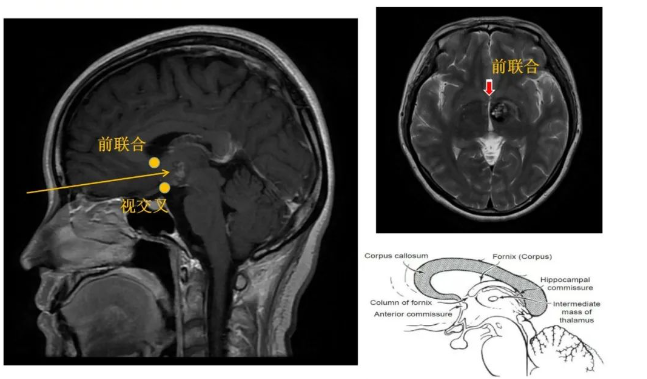

3、肿瘤位置深在,术中导航容易因脑脊液释放引发漂移,术中需以前联合为解剖标记,肿瘤位于前联合后方

经纵裂入路(InterhemisphericCraniotomy)处理下丘脑、中脑病变。纵裂入路开颅术是利用大脑纵裂的自然间隙,进入到大脑镰旁中线深部和脑室旁部位。通过这个自然间隙操作有诸多优点,比如较大限度的降低了对脑组织的牵拉和侵犯。但缘于此操作通道深在而狭窄,该区域的手术充满了技术挑战。这个入路居于冠状缝周围(进行前纵裂入路时)或位于中央小叶的后方(进行顶上纵裂入路时),以保护冠状缝后3-4cm处的躯体感觉运动皮质和众多矢状窦旁优势静脉。

图:经纵裂入路